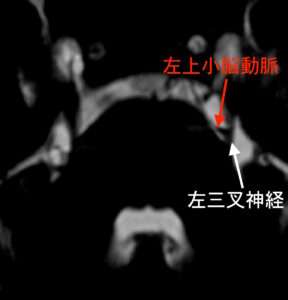

MRIで三叉神経が脳に入る部分を撮像しました。

三叉神経は脳幹という場所に入りますが、斜めに絡まっている血管が見られています。

FIESTA(fast imaging employing steady-state acquisition)という方法で、神経と血管との関係を描き出すと、

すると、左の三叉神経の根元の部分に、左の上小脳動脈という血管が接触しています。そこで、血管の圧迫による三叉神経痛と診断しました。